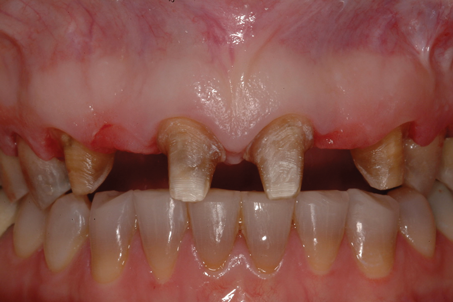

A patient presented with two defective 3-unit fixed partial dentures spanning teeth Nos. 6 through 8 and teeth Nos. 9 through 11 (Figure 7). The defective fixed partial dentures were removed (Figure 8), an impression was made, and traditional provisional fixed partial dentures without ovate pontics were placed. After the impression was sent to the laboratory, the lab technician prepared ovate pontic sites on the stone cast (Figure 9) and fabricated the new definitive bridges. On the day of insertion, the provisional fixed partial dentures were removed (Figure 10), ovate pontic sites were prepared using a teardrop-shaped diamond bur (Figure 11), and the sites were sounded to confirm that there was at least 2 mm from the base of the pontic site to the alveolar bone (Figure 12). The fixed partial dentures were cemented, and the postoperative healing was uneventful (Figure 13).

(8.) Retracted close-up view after removal of the defective fixed partial dentures.

Figure 8